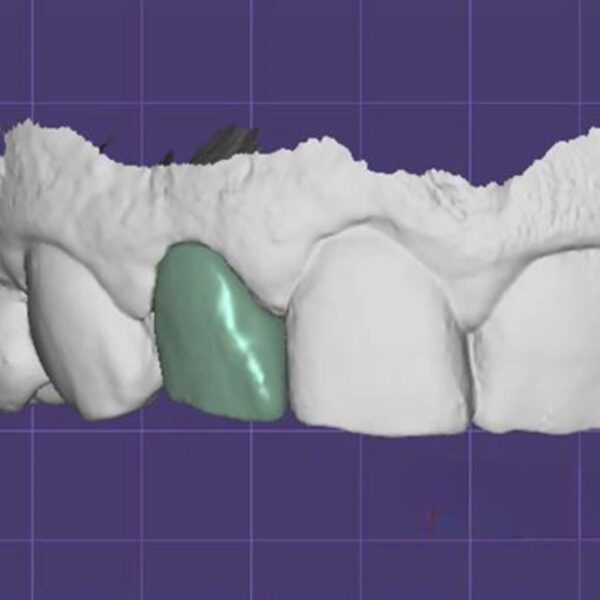

Dental Inlay CAD Design Service (Class I, II & MOD)

Conservative designs with perfect internal adaptation.

- Scope: Class I, Class II (MO/DO), and MOD Inlays.

- Materials: E.max, Composite, Hybrid Ceramics (Lava Ultimate).

- Engineering: Drill Radius Compensation to prevent binding.